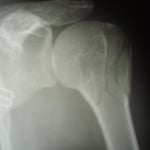

●右鎖骨骨折

当患者さんは手術療法に強く抵抗があり当院での保存療法を選択されました。

骨折部位の短縮転移があたので整復操作が必須になります。運よく短縮転移が矯正されたので保存療法で経過をみました。暑い時期だったので来院の度に固定を外し体を清拭して施術後、新しい下着の上から再度固定をする運びになりました。

骨折部位には超音波、患部以外の所は関節運動、経過を見て軽いマッサージを開始。固定も少しずつ簡易な物へ変更し二カ月後には三角巾のみ、三ヵ月経過すると肩関節の挙上もできるようになりました。

経過良好で完治しました。

左のレントゲンは短縮転位 (受傷時) 右は整復操作をして骨片が重なり合っている状態